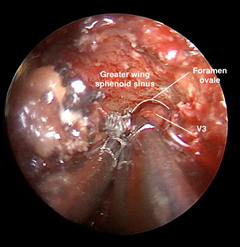

He underwent combined surgery for resection of the skin lesion, with clear margins on frozen section, and transnasal endoscopy for V3 nerve biopsy. At this stage, a post-lacrimal maxillectomy was performed with resection of the body of the right inferior turbinate down to the floor of the nasal cavity, thus providing better exposure of the posterior wall of the right maxillary sinus. A window was made into the posterior wall of the maxillary sinus, removing part of the underlying bone and periosteum to expose the structures of the pterygopalatine fossa. With the aid of the bipolar electrocautery and microdissection instruments, the relevant neurovascular structures (such as the pterygopalatine ganglion, foramen rotundum, internal maxillary artery and its branches) were isolated. This was followed by cauterization of the internal maxillary artery for hemostasis and better visualization of the operative field. The greater wing of the sphenoid was identified and dissected in the subperiosteal plane until the foramen ovale and CN V3 were visible (Figure 6). Finally, with the aid of grasping forceps, a biopsy of CN V3 was performed. Frozen sections identified carcinoma infiltrating nervous tissue. The final histopathological diagnosis was poorly differentiated squamous cell carcinoma.

Figure 6 Transnasal exposure (zero-degree endoscope) of the foramen ovale after dissection of the greater wing of the sphenoid on the right.